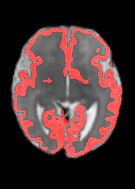

Fetal cortical plate segmentation is essential in quantitative analysis of fetal brain maturation and cortical folding. Manual segmentation of the cortical plate, or manual refinement of automatic segmentations is tedious and time-consuming. Automatic segmentation of the cortical plate, on the other hand, is challenged by the relatively low resolution of the reconstructed fetal brain MRI scans compared to the thin structure of the cortical plate, partial voluming, and the wide range of variations in the morphology of the cortical plate as the brain matures during gestation. To reduce the burden of manual refinement of segmentations, we have developed a new and powerful deep learning segmentation method. Our method exploits new deep attentive modules with mixed kernel convolutions within a fully convolutional neural network architecture that utilizes deep supervision and residual connections. We evaluated our method quantitatively based on several performance measures and expert evaluations. Results show that our method outperforms several state-of-the-art deep models for segmentation, as well as a state-of-the-art multi-atlas segmentation technique. We achieved average Dice similarity coefficient of 0.87, average Hausdorff distance of 0.96 mm, and average symmetric surface difference of 0.28 mm on reconstructed fetal brain MRI scans of fetuses scanned in the gestational age range of 16 to 39 weeks. With a computation time of less than 1 minute per fetal brain, our method can facilitate and accelerate large-scale studies on normal and altered fetal brain cortical maturation and folding.